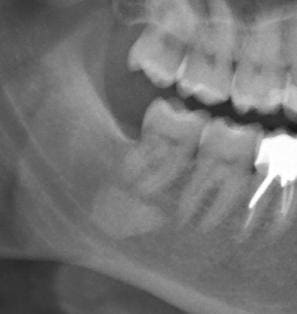

Un OPT de routine chez mon conjoint et voilà l'image retrouvée au niveau des apex de 47/48.

J'ai fait une rétro alvéolaire pour écarter la possibilité d'un artéfact.

J'ai joint les deux images.

Le tout est asymptomatique. Pas de voussure.

Diagnostic?

Cémentome

énostose

- cémentome ou cémentoblastome ou dysplasie cémentaire péri-apicale.

Il s’agit d’une tumeur bénigne.

Un cémentome n'est-il pas toujours en continuité avec la dent?

On voit la continuité sur la rétro, mais pas sur la pano effectivement...

Très juste, c'est justement le critère diagnostic, donc pas de cémentome (terme qui est censé tomber en désuétude au passage) par ici et c'est pourtant assez net sur la pano.

Vu les différences de projection à la radio, on peut penser que ça n'est pas dans le plan vertical que la dent. Je pense à la glande sous-mandibulaire...

Si c'etait du cement il ne devrait pas y avoir de ligament alveolaire visible non?